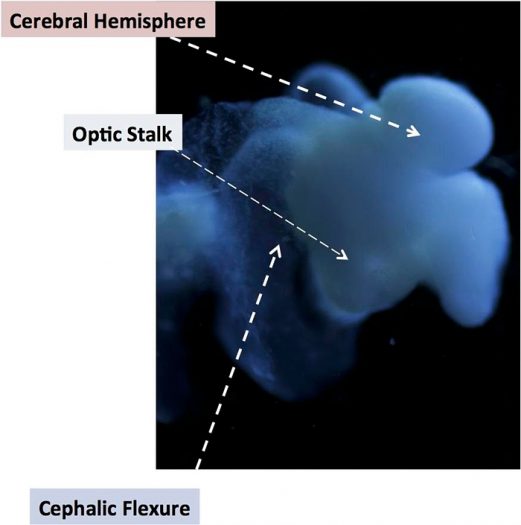

ادامهی نوشتهساخت کاملترین نمونه از مغز انسان در آزمایشگاه

نوروسافاری| گروهی از دانشمندان اعلام کردهاند برای اولین بار موفق به ایجاد یک مغز کامل انسان در آزمایشگاه شدهاند، مغزی که میتوان از آن برای تست داروها و مطالعه روی بیماریهای مختلف استفاده کرد. به گزارش نوروسافاری به نقل از همشهری آنلاین، دانشمندان دانشگاه اوهایو میگویند برای اولین بار …